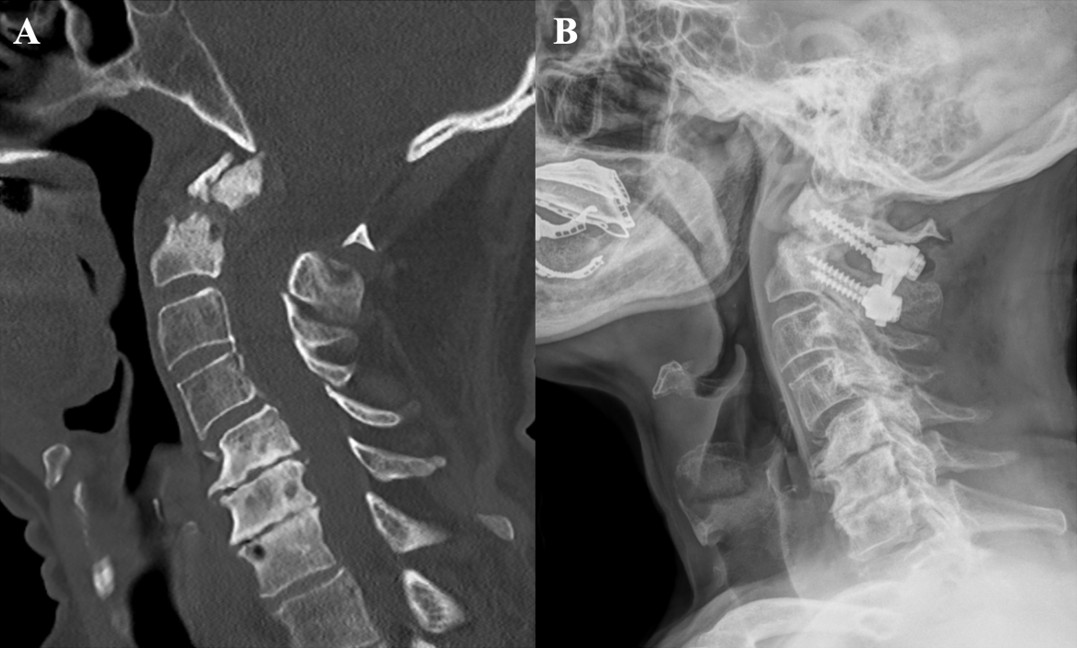

Yöntemler: Bu retrospektif çalışmaya, 2018–2023 yılları arasında üçüncü basamak bir beyin cerrahisi merkezinde tedavi edilen 65 odontoid kırıklı hasta dahil edildi. Kırıklar, Anderson ve D’Alonzo sınıflamasına göre değerlendirildi; Tip II kırıklar ayrıca Grauer sınıflaması kullanılarak alt gruplara ayrıldı. Yaş, travma mekanizması, kırık alt tipi, tedavi yöntemi ve radyolojik sonuçlar gibi klinik veriler analiz edildi.

Bulgular: Hastaların ortalama yaşı 61,9 yıl olup, olguların %56,9’u ≥65 yaşındaydı. En sık travma mekanizması, özellikle yaşlı hastalarda görülen düşük enerjili kendi seviyesinden düşmelerdi (%50,7). Anderson ve D’Alonzo sınıflamasına göre en sık Tip II kırıklar (%53,8) saptanırken, bunu Tip III kırıklar (%44,6) izledi. Tip II kırıkların %82,5’i Tip IIB alt grubundaydı. Hastaların %33,8’ine cerrahi tedavi uygulanmış olup, en sık tercih edilen yöntem anterior odontoid vida fiksasyonuydu. Hastaların %66,2’si ise konservatif olarak tedavi edildi. Bilgisayarlı tomografi ile yapılan takiplerde (n=42) füzyon oranı %76,1 olarak bulundu. Cerrahi tedavi uygulanan hastalarda füzyon oranı %84,2 iken, konservatif tedavi edilenlerde %69,5 idi. Füzyon oranı, 65 yaş altı hastalarda (%81,8) yaşlı hastalara (%70) kıyasla daha yüksek bulundu.